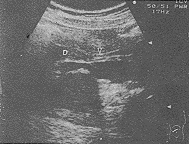

纵旋转扫查法多采用左侧卧位,探头自肝门部向下追踪至胰头,显示其背侧胆管,此时顺时针旋转探头足侧端约30°~60°,使C3、C4得以连续显示(见图1、2)。

胰头(PH)背侧显示胆管(↓↓),末段进入十二指肠(DU),背侧为下腔静脉(IVC)

, 百拇医药

图1 纵旋转法显示胆管全程

胰头(PH)背侧显示胆管(↑↑)

进入十二指肠(DU)

图2 横旋转法显示C3、C4段胆管